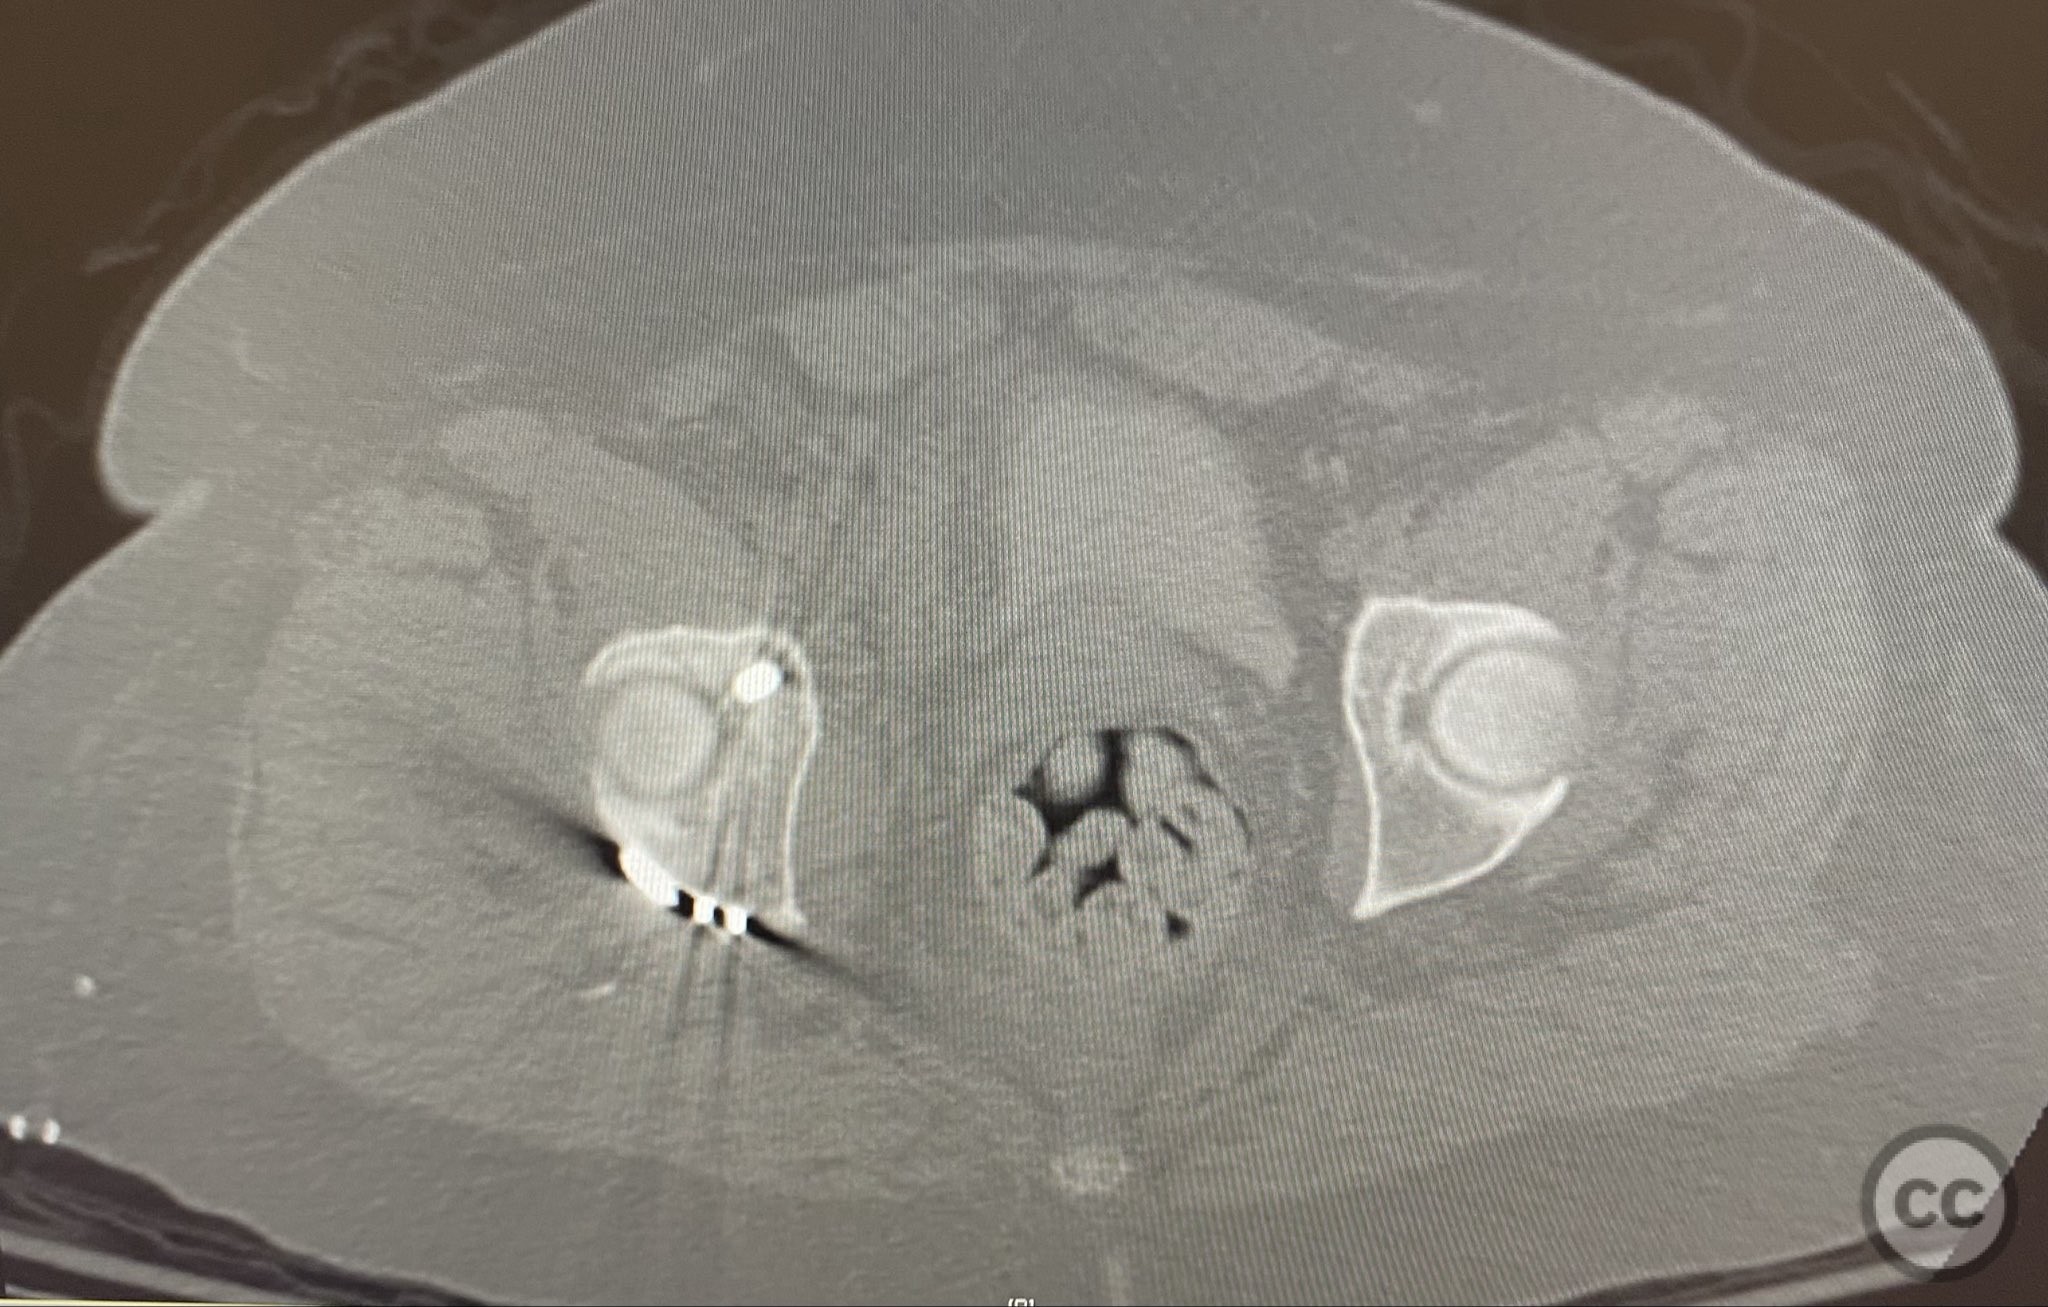

Clinical and radiological findings:  A high-speed motor vehicle collision resulted in a closed transverse acetabular fracture with associated comminuted posterior wall (PW) fracture-dislocation. The femoral head exhibited impaction and comminution, with local cancellous bone crushed and the femoral head itself also sustaining compressive injury from the denser acetabular bone. Neurovascular examination was unremarkable. Initial CT imaging delineated the acetabular fracture planes, displacement, comminution of the posterior wall, femoral head impaction, and absence of soft tissue attachment to the caudal PW fragment.

The transverse fracture was manipulated and temporarily stabilized using a reduction clamp applied across the fracture plane. Under biplanar fluoroscopic guidance, a cannulated cancellous lag screw was percutaneously inserted to achieve interfragmentary compression across the transverse component. The reduction clamp was then removed. Posterior wall fragments were anatomically reduced and stabilized with contoured buttress plates spanning both the posterior wall and providing additional stabilization to the transverse component. Postoperative CT confirmed satisfactory reduction and fixation of both acetabular columns and restoration of articular congruity.